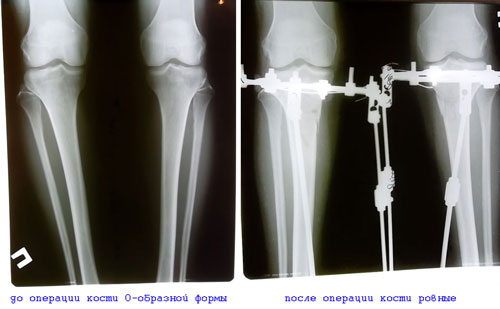

Рентгеновские снимки Mara

Вложения

SAM_3173.JPG

Диагноз: О-образная деформация ног

ИСХОДНИК

В аппаратах Илизарова-Онипко